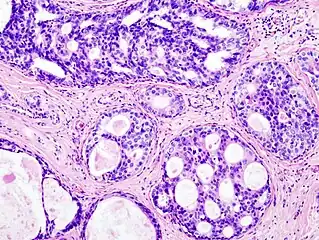

Histopathologic architectural patterns of DCIS.[26]

Histopathologic image from ductal cell carcinoma in situ (DCIS) of breast. Hematoxylin and eosin stain.